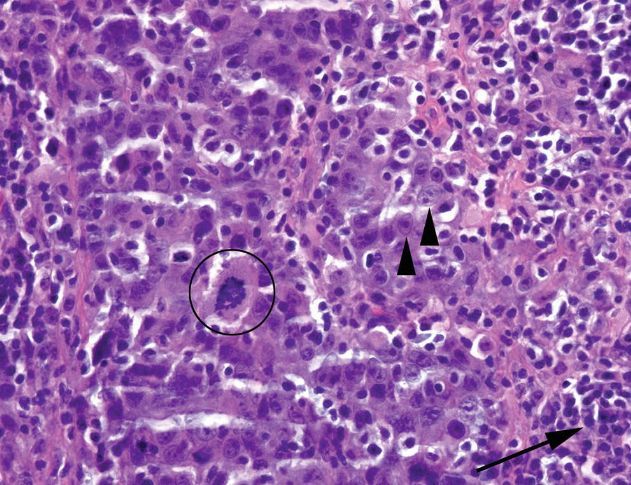

Lymphoepithelial-like carcinoma

Gives off an overall impression of raging inflammation and tissue destruction. Sheets of lymphocytes are present. But, the actual carcinomatous cells tend to fade into the background.

The nuclei are large and bubbly and not particularly hyperchromatic or carcinoma-like. The cytoplasmic borders are indistinct, almost syncytial. Atypical mitoses may be present.

A cytokeratin stain is helpful.